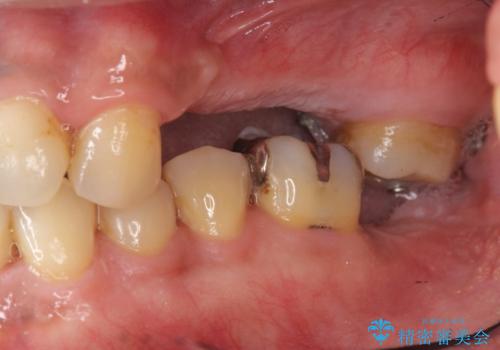

- 長期間放置してしまった虫歯の治療を希望され来院されました。

・重度虫歯による残根状態・欠損歯→インプラント補綴

・対合歯の欠損による歯の挺出→マイクロインプラントを用いた小矯正を行うことで咬合平面を是正

噛み合う歯が欠損し長時間放置すると、歯が挺出(歯が伸びてくる)し欠損補綴を行おうにもスペースが足りない場合があります。(クリアランスの不足)

加えて咬合平面の乱れを放置したまま無理やり補綴治療を行うと、特定の部位に過大な力がかかり当該歯を痛めてしまうこともよくあります。